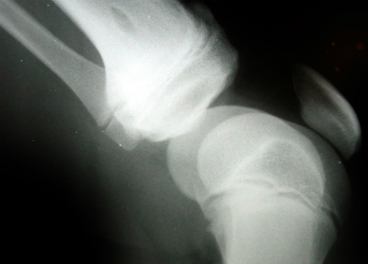

Un estudio español demuestra la acción positiva del aceite de oliva en los huesos. Revista Olimerca. Publicado em 3 de dezembro de 2015 por admin Actúa sobre la elasticidad y la biomecánica ósea Fonte: Un estudio español demuestra la acción positiva del aceite de oliva en los huesos. Revista Olimerca.